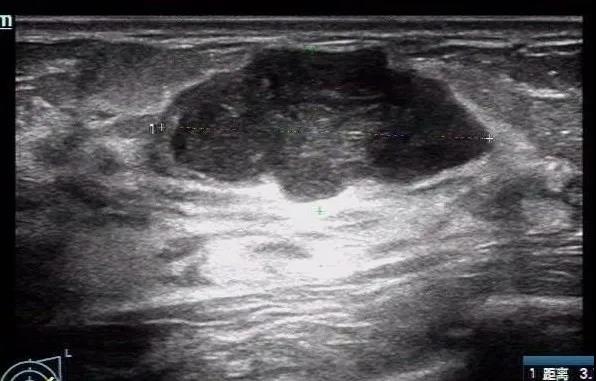

恶性叶状肿瘤:年龄45,边界清,稍不规则,未见明显血流,与良性肿瘤鉴别困难,考虑到年龄大,病史肿块逐渐增大,需要考虑到叶状肿瘤的可能性。